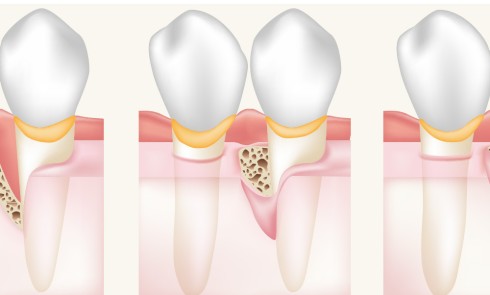

Défauts intra-osseux

Article réservé à nos abonnés Chirurgie parodontale régénératrice : incisions et sutures des lambeaux de préservation papillaire

Au cours des trois dernières décennies, des progrès significatifs ont été réalisés en chirurgie parodontale régénératrice. L’évolution principale réside dans...